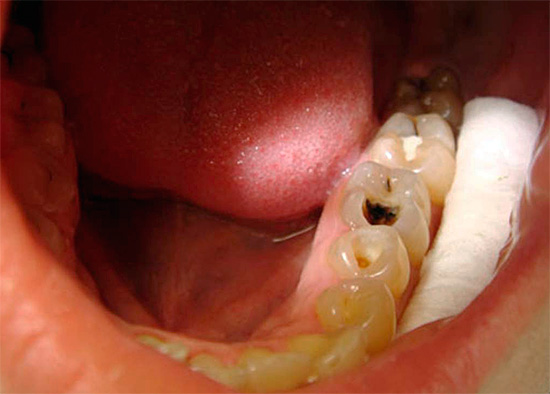

Foto de um dente com uma cárie profunda que atinge a câmara pulpar:

Sujeito a disponibilidade cavidade cariada profunda, que se comunica com a câmara pulpar, as dores podem não incomodar ou aparecer apenas ao mastigar alimentos duros devido à irritação mecânica do "nervo". Histórias de casos semelhantes com pulpite fibrosa crônica são observadas no caso da localização da cavidade cariosa além do acesso de substâncias irritantes, por exemplo, sob a gengiva (cárie radicular).

Geralmente, no dente, há uma cavidade profunda e cárie com dentina infectada amolecida, que freqüentemente se comunica com a câmara pulpar.Para esclarecer a presença dessa mensagem, o dentista usa uma sonda - um instrumento de metal curvo e afiado no final da sondagem.

O diagnóstico por raio-X também é importante. Na pulpite fibrosa crônica, uma cavidade profunda de cárie, que quase sempre se comunica com a câmara pulpar, geralmente pode ser observada na radiografia de um dente doente. Às vezes, uma ligeira expansão do espaço periodontal (o espaço entre a raiz e o osso dos alvéolos nos quais está fixado) é fixada.